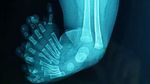

Dokter di Aceh menemukan kasus langka mirror foot dan polidaktili pada seorang bayi sehingga memiliki sepuluh jari di kaki kirinya. Kondisi ini juga disertai kelainan kaki pengkor dan lutut melengkung ke belakang. (Foto: Journal of International Surgery and Clinical Medicine (JISCM))

Bayi berusia tiga bulan itu diketahui memiliki struktur tulang kaki yang ikut bertambah, termasuk sembilan metatarsal. Hasil radiologi menunjukkan seluruh tulang jari terbentuk sempurna dan berfungsi seperti jari normal. (Foto: Journal of International Surgery and Clinical Medicine (JISCM))